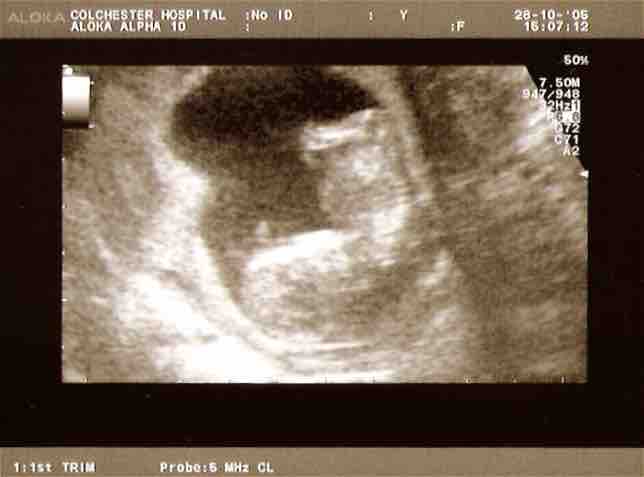

Ultrasound scan

Ultrasound is used to monitor the age and health of the fetus during pregnancy.

This is an ultrascan scan of a fetus.